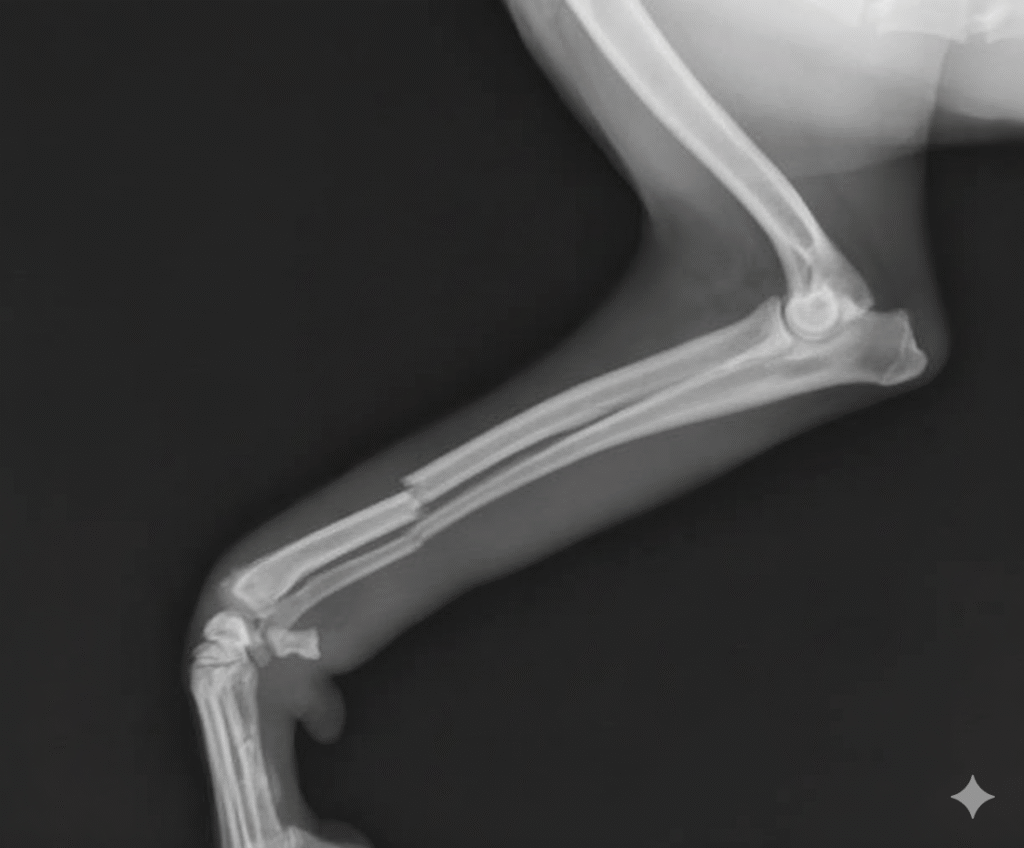

De dierenarts doet eerst een kort lichamelijk onderzoek om de breuk vast te stellen. Vervolgens zal de hond worden meegenomen naar de röntgenkamer voor de CT-scan.

Wanneer de diagnose klopt, gaat de hond onder narcose. De dierenarts gaat aan de slag om het bot op zijn plaats te zetten. Na afloop van de operatie gaat het gips eromheen.